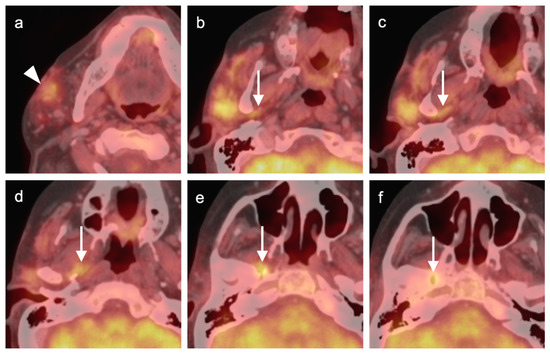

2.2. Squamous Cell Carcinoma of the Head and Neck (SCCHN)

2.3. Nasopharyngeal Carcinoma

2.4. Sinonasal Tumors